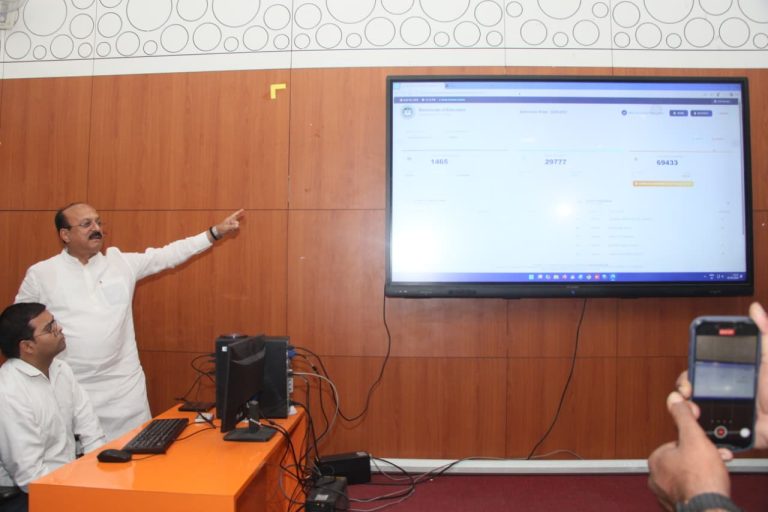

सोहना, (आई.डब्ल्यू.एन.ए). : आम जनमानस को कैंसर की बीमारी से जागरूक बनाने के लिए विश्व कैंसर दिवस के उपलक्ष्य में बुधवार को स्वामी विवेकानंद आरोग्य केन्द्र परिसर में एक दिवसीय जागरूकता शिविर का आयोजन हुआ। स्वामी विवेकानंद आरोग्य केन्द्र के महासचिव विवेकानंद तिवारी की अध्यक्षता में आयोजित कैंसर से बचाव वाले इस जागरूकता शिविर में बोलते हुए कैंसर रोग विशेषज्ञ डाक्टर प्रिया तिवारी ने उपस्थितों के साथ-साथ आम जनमानस को कैंसर रोग के प्रति जागरूक करते हुए बताया कि कैंसर रोग शरीर में कही भी और किसी भी उम्र में हो सकता है। ज्यादातर यह रोग गले, फेफड़े, मुंह, महिला के स्तनों व बच्चादानी में होता है। अगर समय से रोग का निदान कर लिया जाए तो इसका उपचार संभव है। उन्होंने कहा कि कुछ समय पूर्व तक कैंसर को असाध्य रोग माना जाता था। अब इसका ना केवल इलाज संभव है बल्कि कैंसर की जल्द पहचान होने पर बहुत ही बेहतर और सस्ता इलाज भी आज उपलब्ध है। उन्होने बताया कि अनेकों कैंसर पीडि़त रोगियों ने इस रोग से लड़ते हुए उस पर जीत भी हासिल कर अन्य कैंसर पीडि़त रोगियों के लिए मिसाल कायम कर जीवन जीने की उमंग जगाई है। कैंसर रोग विशेषज्ञ डाक्टर प्रिया तिवारी ने हार्ट और कैंसर से बचाव के लिए प्रत्येक मनुष्य को अपने लाइफ स्टाइल में बदलाव ला प्रतिदिन नियमित रूप से शारीरिक व्यायाम करने, अपने वजन पर संतुलन रखने, वसायुक्त भोजन से परहेज करने, ताजी हरी सब्जियों, फलों का सेवन करने, बीड़ी, सिगरेट, तंबाकू, शराब, मदिरापान, प्रदूषण, दूषित, बासे खाद्य पदार्थों से दूर रहने जैसे परामर्श देते हुए कहा कि आज की भागदौड़ और आपाधापी युक्त तनाव भरी दिनचर्या को अनुशासित रखने, शाकाहारी भोजन के साथ यदि प्राकृतिक खान-पान को अपनाया जाए तो कैंसर से काफी हद तक बचाव संभव है। कैंसर रोग विशेषज्ञ डाक्टर प्रिया तिवारी के अनुसार व्यक्ति को लंबी आयु जीने व निरोगी रहने के लिए फास्ट फूड़ व शराब से दूर रह खानपान में फल व हरी सब्जियों का भरपूर प्रयोग करना चाहिए। शराब व मांस के सेवन से परहेज करना चाहिए। समय-समय पर चिकित्सकों से अपनी शारीरिक जांच करवाते रहे। विवेकानंद आरोग्य केंद्र के महासचिव विवेकानंद तिवारी का कहना है कि भारत विकास परिषद द्वारा संचालित विवेकानंद आरोग्य केंद्र में हृदय रोग संबंधी उपचार के साथ-साथ महंगी-महंगी स्वास्थ्य संबंधी जांचें सरकारी रेट से भी कम नाममात्र में होने से निर्धन तबके के लोग खासे खुश है। यहां पर सीटी स्कैन के साथ-साथ सारे ब्लड टैस्ट, मल-मूत्र जांच, ईको, स्टे्रस ईको, टीएमटी, अल्ट्रासाउंड, ओपीजी, मैमोग्राफी, एक्स-रे, ईसीजी, शुगर टैस्ट, ईईजी सीटी स्कैन, कैंसर का इलाज और कीमो जैसी सुविधाएं उपलब्ध कराई जा रही है। इतना ही नही सीटी स्कैन मशीन की सुविधा जरूरतमंदों के लिए मुहैया करा दी गई है। विवेकानंद आरोग्य केंद्र के महासचिव विवेकानंद तिवारी ने बताया कि भारत विकास परिषद द्वारा संचालित विवेकानंद आरोग्य केंद्र को नर सेवा-नारायण सेवा के ध्येय को लेकर चलाया जा रहा है। इसी के तहत इसके जांच की कीमत सरकारी रेट से भी कम रखी गई है। उन्होने जरूरतमंदों से आग्रह किया कि जिस भी जरूरतमंद रोगी को अपना सिटी स्कैन करवाना हो विवेकानंद आरोग्य केन्द्र सैक्टर बारह माधव भवन के पास जाकर करवा सकता है। विवेकानंद आरोग्य केंद्र के महासचिव विवेकानंद तिवारी ने सर्वजातीय समाज के जागरूक लोगों से भी आग्रह किया है कि भारत विकास परिषद द्वारा संचालित विवेकानंद आरोग्य केंद्र में सरकारी कीमत से भी कम दामों में विभिन्न जांच किए जाने संबंधी जानकारी मध्यम वर्ग व निर्धन वर्ग के साथ-साथ जरूरतमंद रोगियों को जरूर दे ताकि वह नाममात्र की दरों पर अपनी जरूरी जांच कराकर अपना समुचित उपचार करा सके और स्वास्थ्य लाभ ले सके। आरोग्यधाम में ईको कराने आए एक रोगी ने बताया कि जो ईको निजी अस्पताल में 3 हजार 850 रुपए में होता है और निजी लैबों पर कई-कई घंटे इंतजार के बाद यह ईको 2 हजार 850 रुपए में किया जाता है, वही ईको आरोग्यधाम में मात्र एक हजार 100 रुपए में सहज रूप में उनका हो गया है। ईसीजी मात्र 80 रुपए में तत्काल रूप में की जा रही है। इसी तरह और भी काफी सारी ऐसी जांचें है, जिनकी कीमतें आरोग्यधाम में सरकारी अस्पतालों की कीमतों से भी बहुत ही कम रखी गई है और अत्यंत निर्धन वर्ग के रोगियों की पहुंच में है। इस मौके पर डायबिटीज रोग विशेषज्ञ डाक्टर एनडी बंसल व डाक्टर अशोक गुप्ता, हडडी रोग विशेषज्ञ डाक्टर मनोज कुमार, नेत्र रोग विशेषज्ञ डाक्टर शिवम सेठी, हृदय रोग विशेषज्ञ डाक्टर नितिन पाराशर, चर्म रोग विशेषज्ञ डाक्टर मुकेश रामपाल, राष्ट्रचिंतक कैलाश गर्ग, सोहना व्यापारमंडल संघ के चीफ एडवाईजर व अग्रवालसभा के वरिष्ठ उपाध्यक्ष रहे उमेश अग्रवाल समेत विवेकानंद आरोग्य केंद्र से जुड़े लोग विशेष रूप से मौजूद रहे।